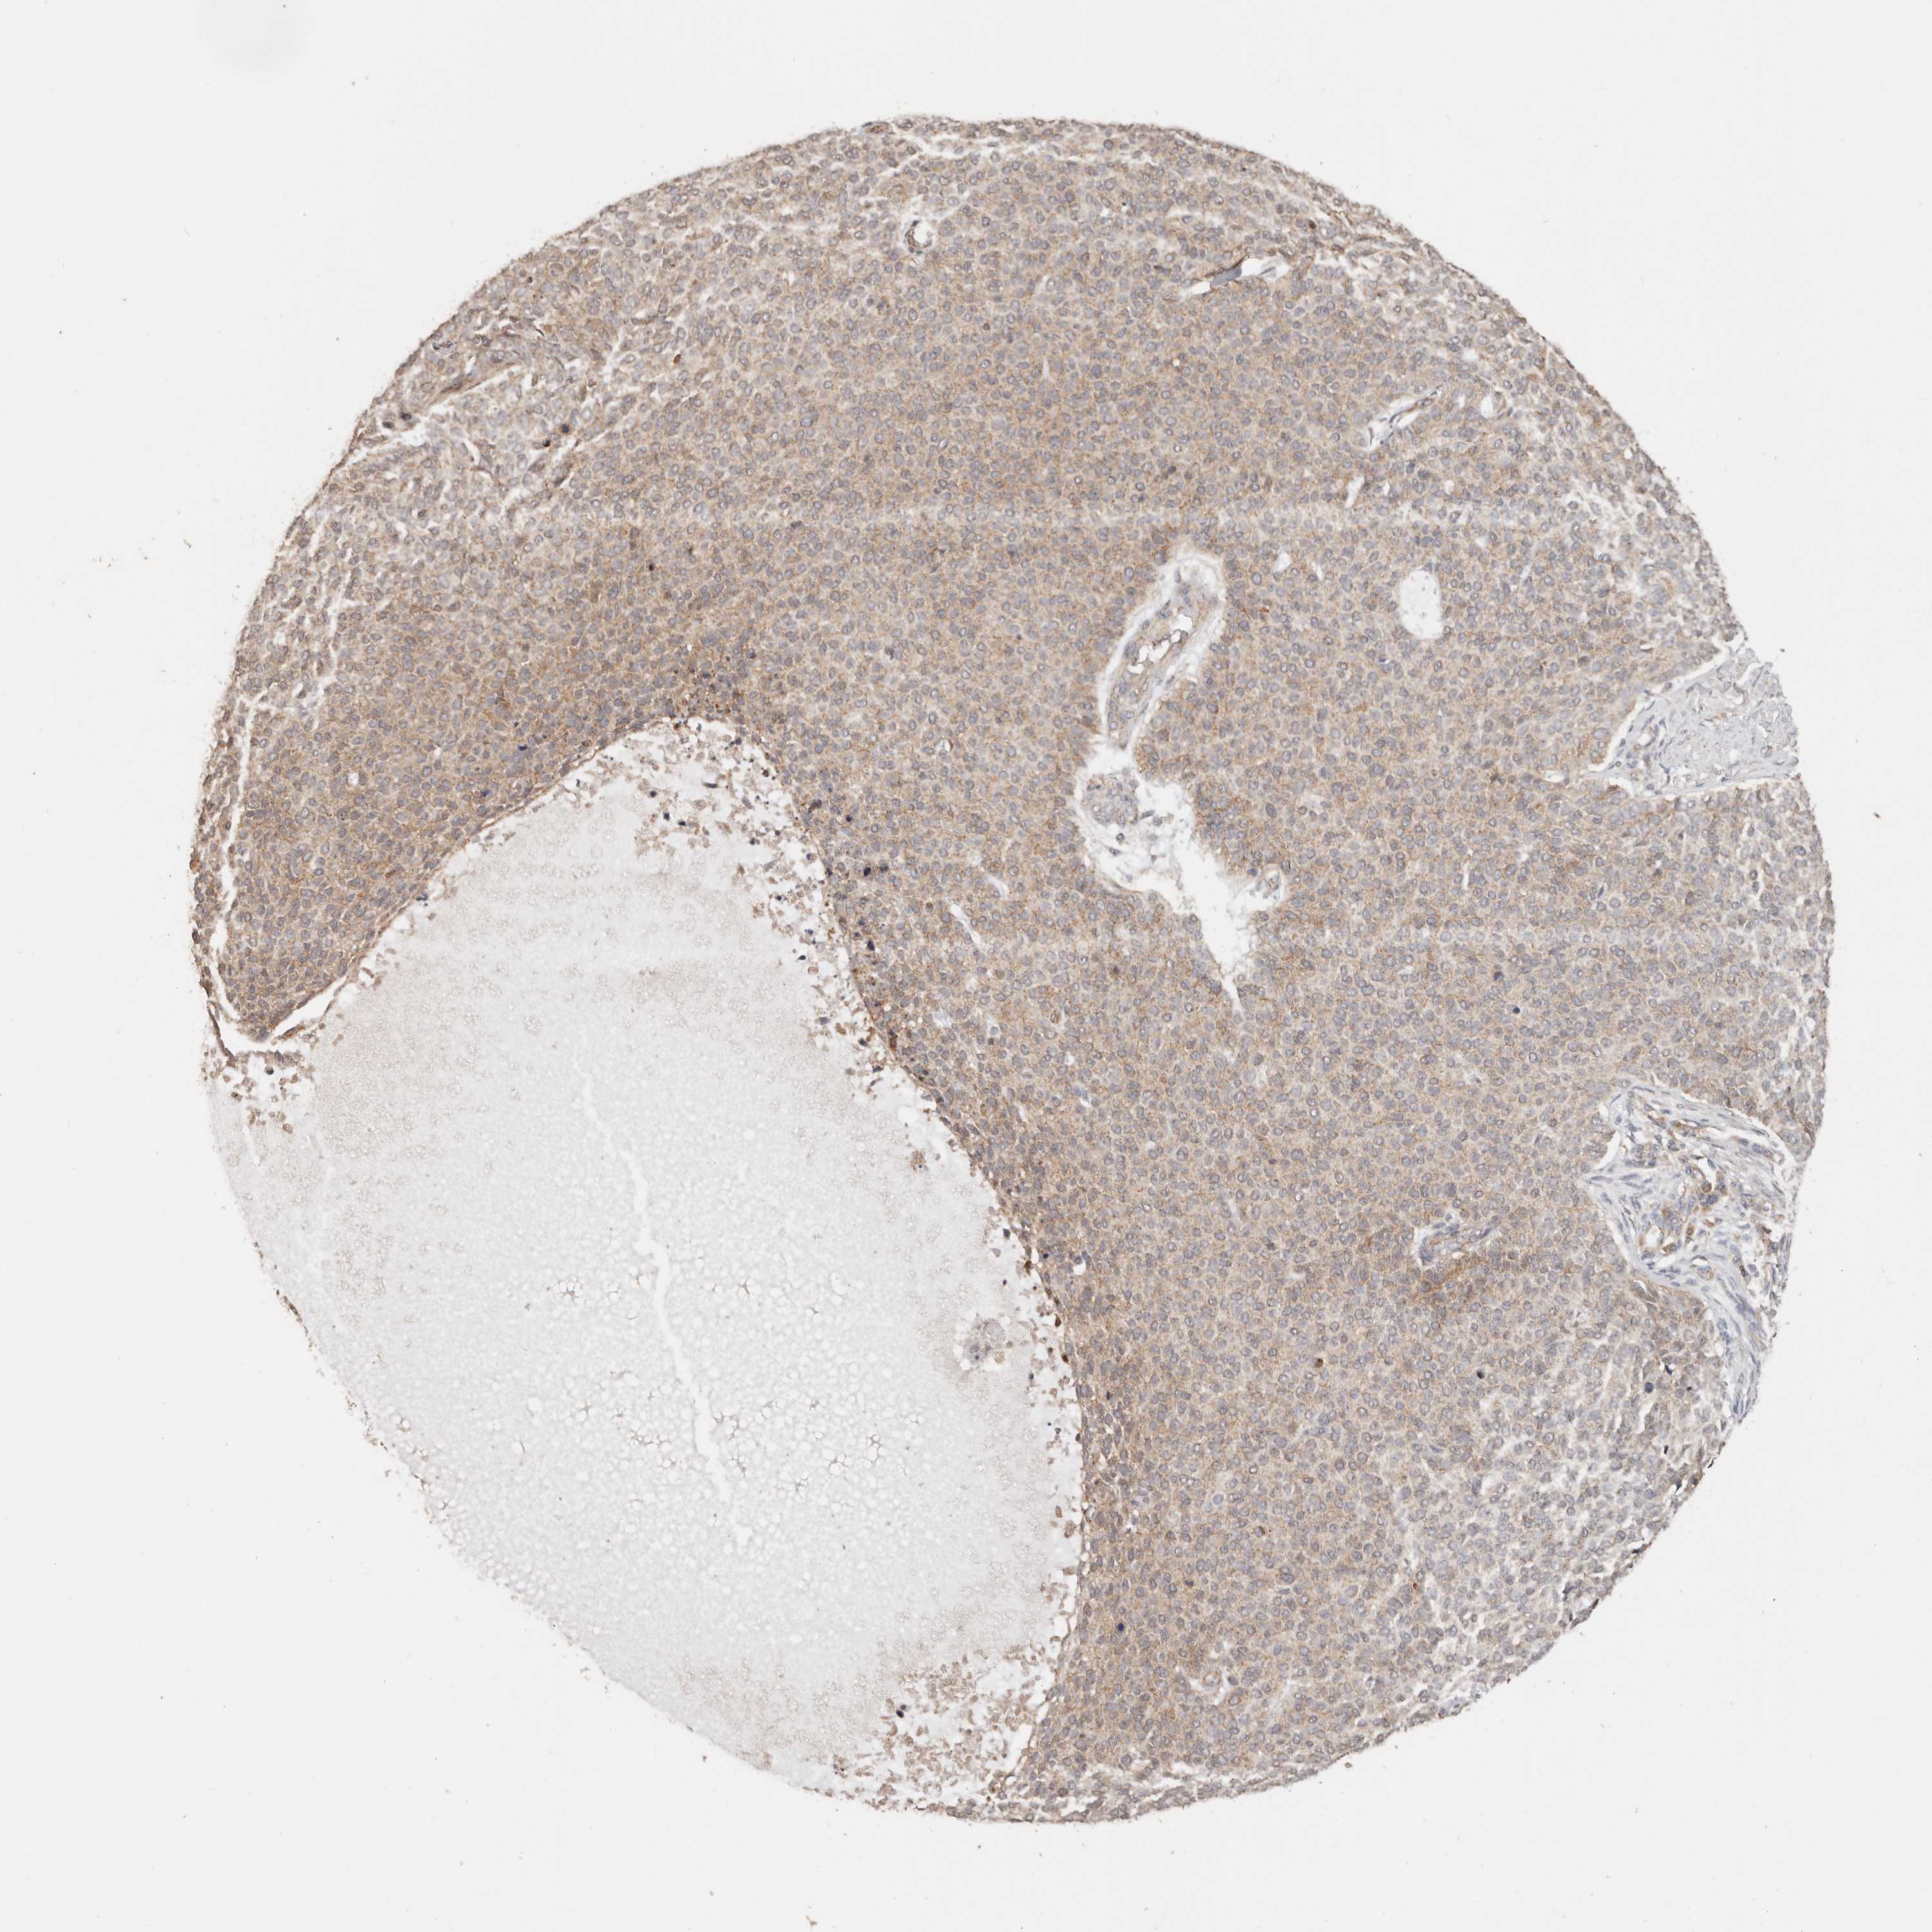

SKIN CANCER - Protein expressioni

A mouse-over function shows sample information and annotation data. Click on an image to view it in a full screen mode. Samples can be filtered based on level of antibody staining by selecting one or several of the following categories: high, medium, low and not detected. The assay and annotation is described here.

Each image is clickable and will lead to virtual microscopy that enables deeper exploration of all samples and also displays staining intensity scores, fraction scores and subcellular localization as well as patient and tissue information for each sample.

HPA030212

HPA030213

HPA030214

HPA030215

CAB013496

Basal cell carcinoma

Squamous cell carcinoma, NOS

Squamous cell carcinoma, metastatic, NOS

Adnexal tumor, benign